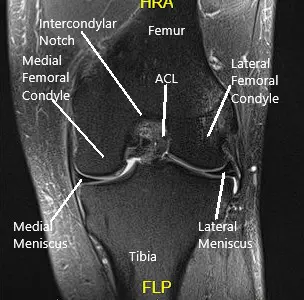

DESCRIPTION OF PROCEDURE:  A lateral entry portal was made.  The scope was entered.  The patellofemoral joint was found to be in good shape with no cartilage damage.  The scope was taken to the medial gutter where there was a synovial flap.  The medial compartment showed a ramp lesion of the posterior body of the medial meniscus.  The root was intact.  There was no cartilage loss.

Intraoperative knee arthroscopic images

Intraoperative knee arthroscopic images.

The medial entry portal was made.  The probe was inserted and the meniscus tear was again checked.  It was involving the posterior body of the medial meniscus along with the capsule.  The decision was made to repair the ramp lesion using an all-inside suture configuration.

Two curved and two reverse curved FasT-Fixes were used to complete the repair after the meniscus was abraded along with a capsule abrasion done with the shaver. The repair was found to be in a good position.